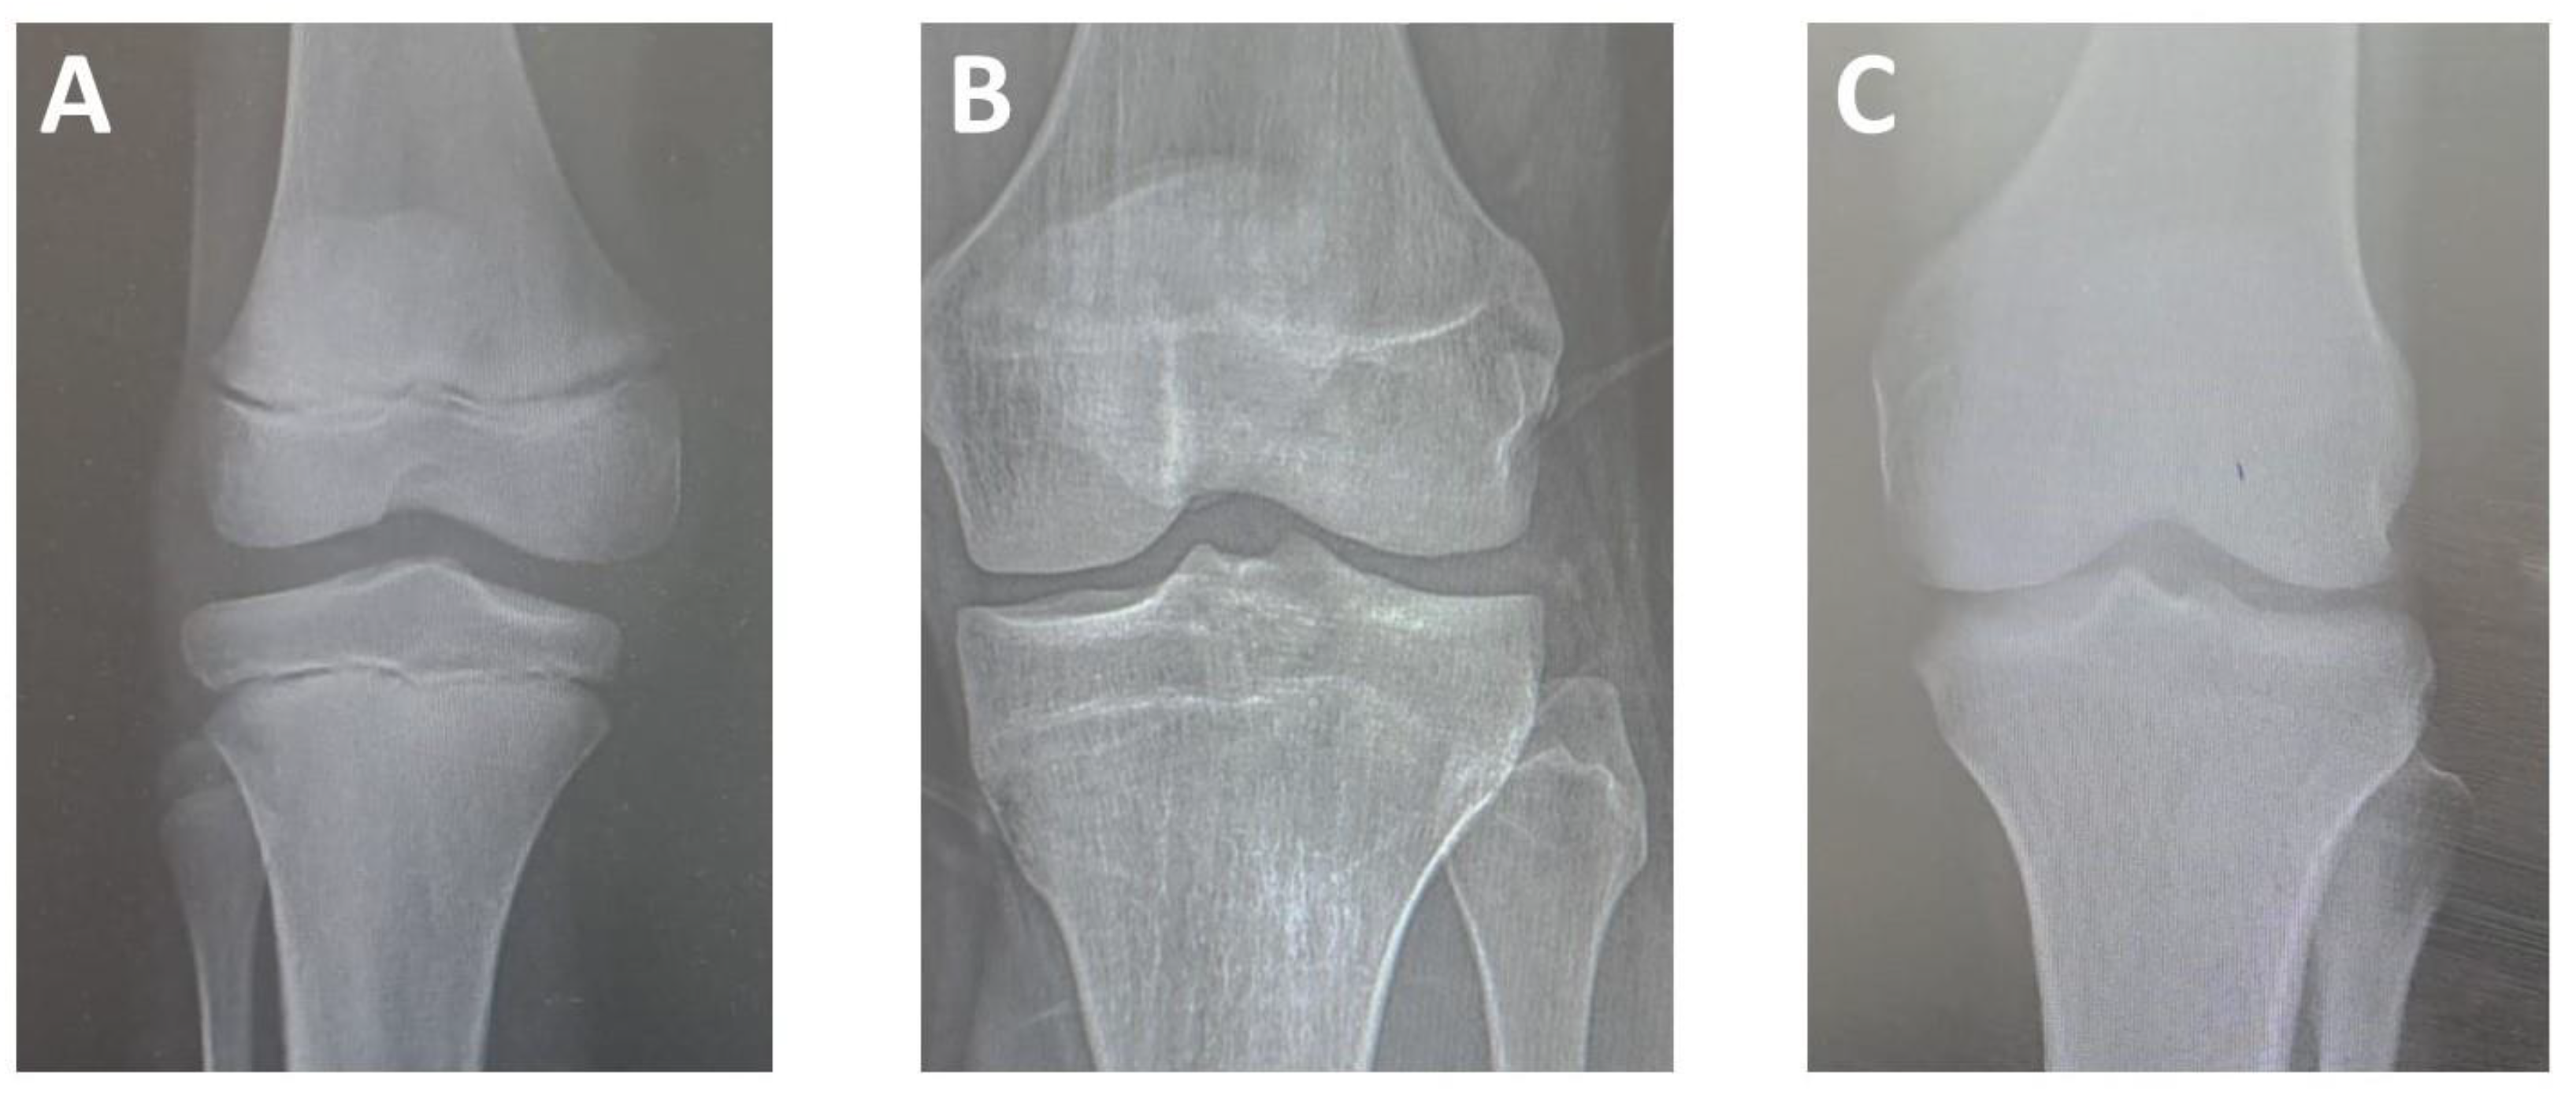

Epiphyseal union was estimated based on the three-level criteria proposed by Cameriere et al. (2012) [12], in which the classification is determined by the degree of epiphyseal ossification and the visibility of the epiphyseal scar, divided into three stages (Figure 1). The epiphyses of the femur, tibia, and fibula near the knee joint (i.e., distal end of the femur, proximal end of the tibia, and proximal end of the fibula) were evaluated from all views. Participants’ chronological age calculations were based on the date of the image and the date of birth. The observers were blinded to the age and sex of all radiographs when determining the stage of epiphyseal union for all bones, and for each stage, a score was assigned. Data from all bones (femur, tibia, and fibula) were averaged. In cases of doubt regarding the union stage, the lower stage was adopted.

Figure 1.

Plain X-ray images of the knee joint showing stages of epiphysis union; (A) Stage I, epiphysis is not fused at the distal end of the femur and the proximal ends of the fibula and tibia; (B) Stage II: epiphysis is fully ossified, and epiphyseal scar is visible at the distal end of the femur and the proximal end of the tibia; (C) Stage III, epiphysis is fully ossified, and epiphyseal scar is not visible at the distal end of the femur and the proximal end of the tibia [12].